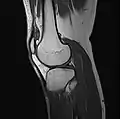

MRI

Both anterior cruciate ligament (ACL) and posterior cruciate ligaments (PCL) are hypointense on both T1 and T2 weighted images of MRI. However, some high signal striations are often seen at the distal part of the ACL, making ACL higher intensity than PCL on MRI scans.[17]